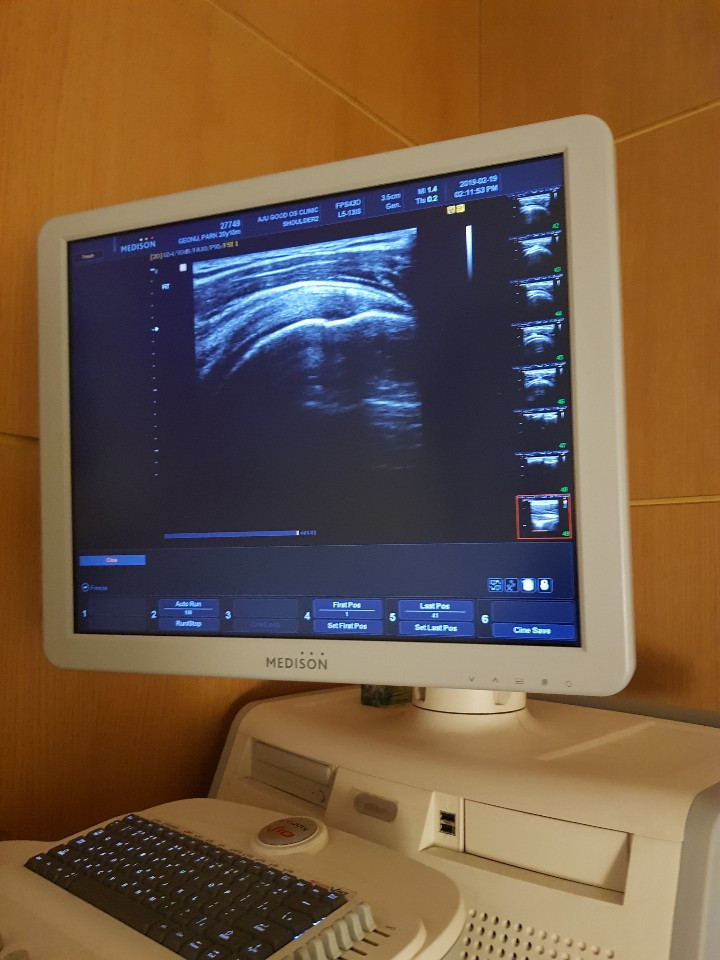

이제는 초음파 화면이 익숙하다

이미 속에서는 짜증과 실망감에 더이상의 정보를 원하지 않았지만 선생님은 초음파와 엑스레이를 준비하셨다.

이제 슬슬 초음파가 눈에 익지 않냐는 선생님의 농담은 한귀로 흘린 채, 화면에 뜬 내 어깨 영상에 집중했다.

다행히 힘줄이 끊어지지는 않았고 군데군데 손상이 간 부분이 있다고 했다. 결국 왼쪽 어깨보다는 조금 나을 뿐

다를것이 없었다.